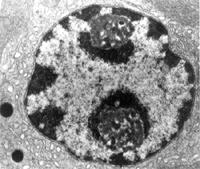

結果兩組睪丸的生精小管內,生精細胞之間均未見明顯裂隙。對照組和庚酸睪酮組分別有89.0%±12.9%和63.5%±20.4%(前一比值顯著高於後者,P0.05)的生精小管輪廓內有成團的生精細胞,細胞團的一側常未與生精上皮完全分離,好像是部分生精上皮呈"c"形突入管腔。細胞團主要由精子細胞和粗線期精母細胞組成,細胞形態基本正常,沒有明顯退化或固縮的細胞;兩個組中分別有9.0%±8.3%和33.6%±18.8%(前一比值顯著低於後者)的細胞團中可見Sertoli細胞核。庚酸睪酮組生精小管內的生精細胞數量減少,有些生精小管輪廓內甚至只剩Sertoli細胞與A型精原細胞;突人管腔的細胞團常較小,精子發生抑制愈嚴重細胞團就趨於愈小,愈少見。圖1對照組(a)和庚酸睪酮組(b)的典型生精小管輪廓,攝自25m厚的甲基丙烯酸樹脂切片。突入管腔的生精細胞團。標尺=5On。